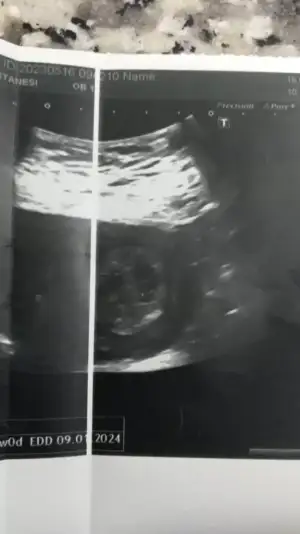

Benimkiler çift yumurta ama aralarında bir hafta fark çıkıyor.Hatta kız kendi haftasından da ilerde erkek daha geride kalıyor.Merhaba ikiz anneleri, ben de 28 haftalık tek yumurta ikizlerine hamileyim. Monokoryonik diamniyotik denilen türden. Aranızda yeniyim.bebeklerin arasında gelişim farklılığı var bu durumu tecrübe edenler oldu mu aranızda. İyi hikayeler duymaya çok ihtiyacım var..

Kızlar merhaba bugun ıkızlerımın detaylı ultrasonu vardı 22 haftalığız bı sıkıntı yok Şükür sağlıklılar gayet